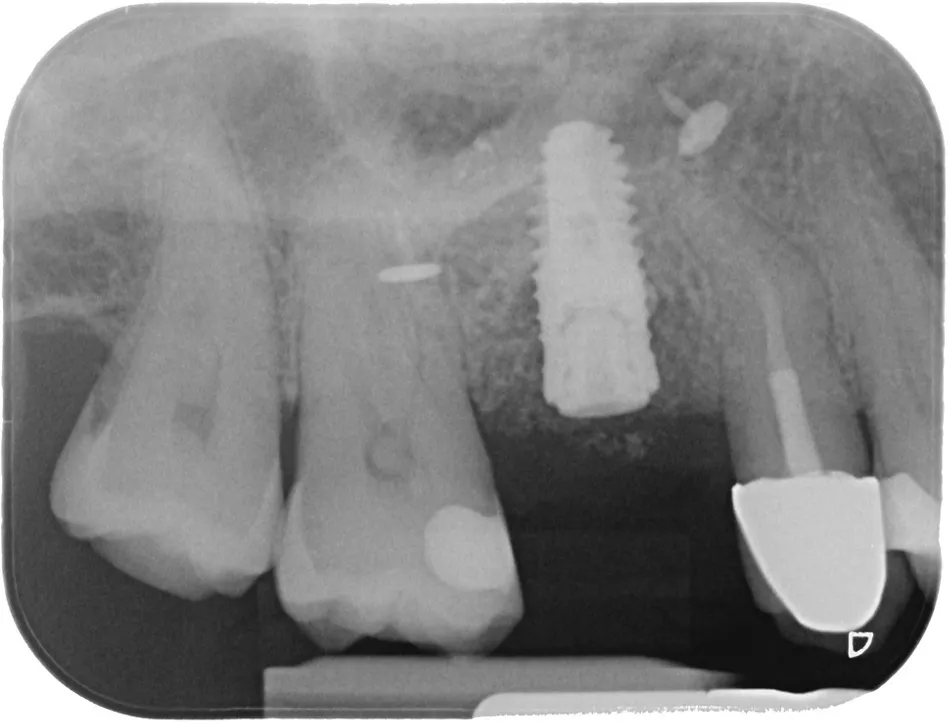

Upon completion of the first-stage surgery, a control radiograph was taken, revealing the membrane fixation pins and confirming that everything was in good condition (Fig. 24).

Fig. 24

Four months after the surgical procedure, a second procedure was performed to remove the screws and improve the soft tissue contour.  A partial-thickness flap was raised for soft tissue management. After reflection of the periosteum, the pins and membrane were extracted, and the previously removed prosthodontic restoration was reinserted (Figs. 25–28).